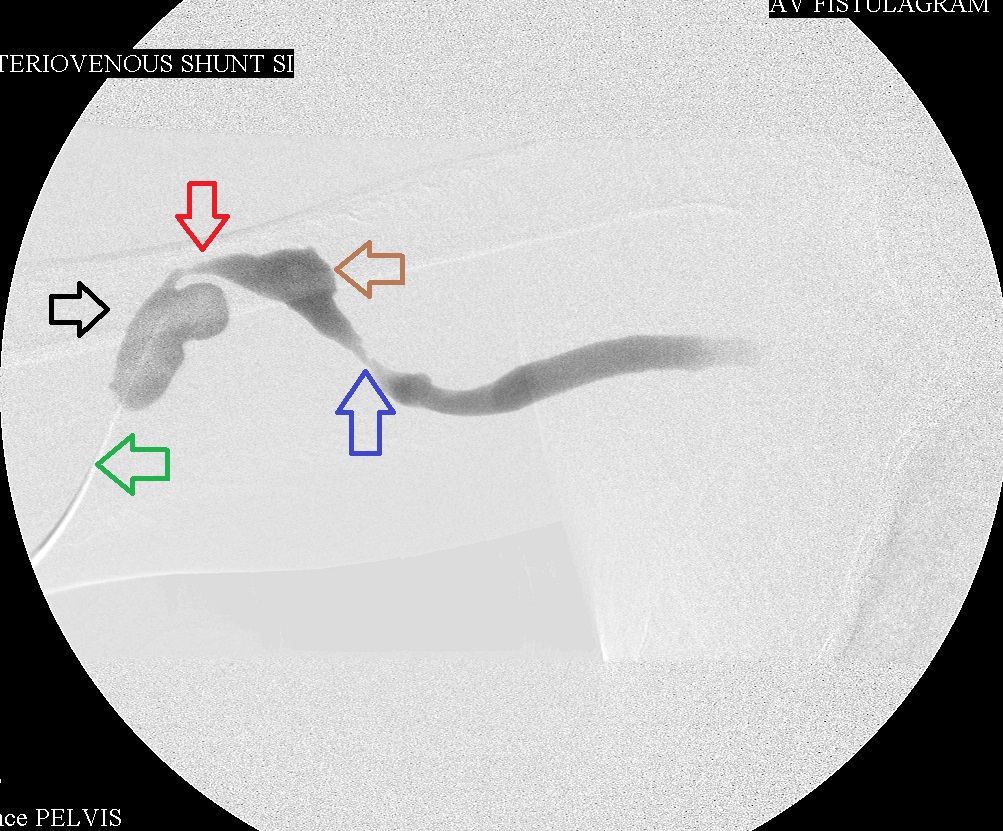

Right brachial venogram before intervention: green arrow is 1st and juxta-anastomotic stenosis; black arrow is proximal aneurysm; red arrow  is 2nd and mid stenosis; brown arrow is 2nd aneurysm; blue arrow is 3rd and distal stenosis.